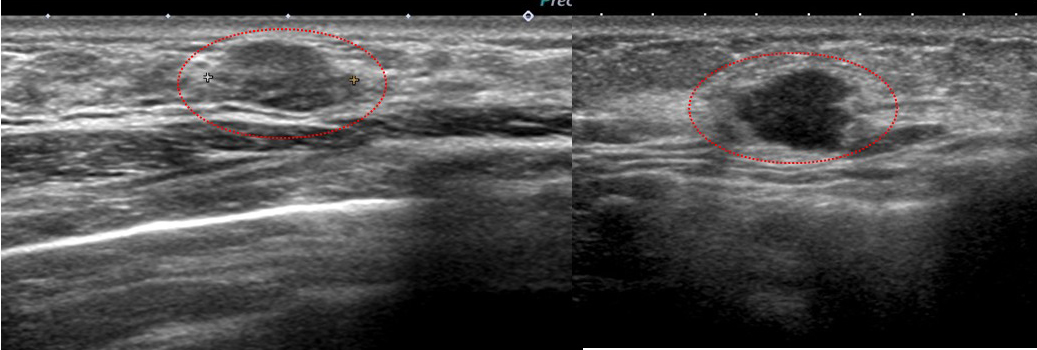

典型的な「線維腺腫(実際に生検で線維腺腫と確認)」と典型的な癌「私のcat.7」を提示します。

左と右、どちらが線維腺腫でどちらが癌なのか?当ててください(皆さんなら簡単ですね? 引っかけはありません)

このくらい典型(私cat. 2)ならば画像だけで「線維腺腫で大丈夫です」と言えるのです。

♯逆にこれくらい典型(私cat. 7)ならば画像だけで癌と言い切ってもいいでしょう。